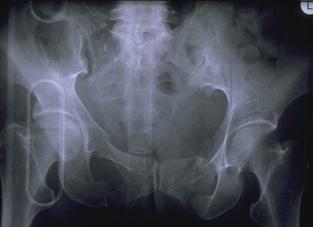

Banda de stabilizare Dallas Fractura de bazin. Radiografie in

incidenta AP

Inaintea

aplicarii benzii de stabilizare Dallas

Fractura de bazin

. Radiografie in incidenta AP Fractura de spina

iliaca antero-superioara

Dupa aplicarea benzii de stabilizare Dallas prin avulsie. - Stabila -